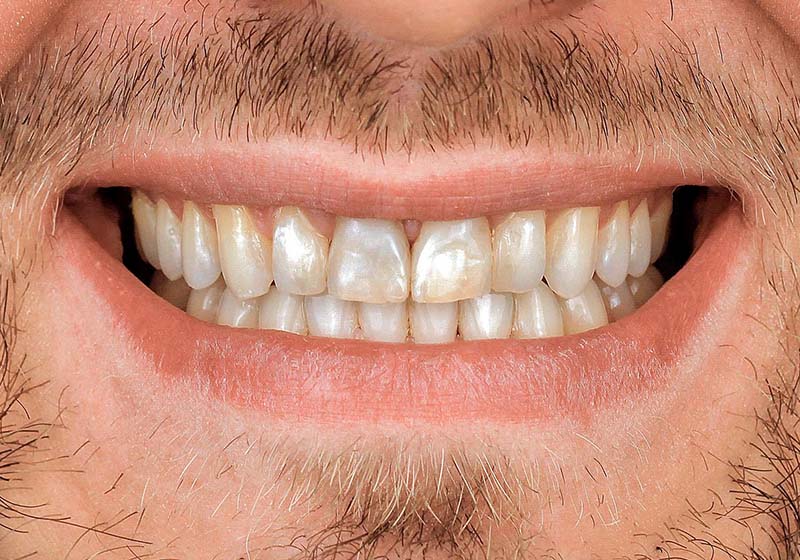

Комплексная реставрация винирами E-max на верхней и нижней челюсти

Проведена полная эстетическая реставрация зубных рядов верхней и нижней челюстей винирами E-max. Восстановлена форма, размер, цвет и поверхность фронтальных зубов, достигнута гармоничная улыбка.